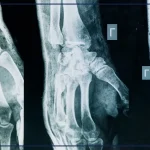

Quando aveva 4 anni era stato sottoposto a due interventi neurochirurgici per una presunta e rarissima forma tumorale al cervello, che gli provocava crisi epilettiche continue. Ma, come hanno accertato le indagini successive, quel tumore non esisteva: si trattava di una infiammazione cerebrale che avrebbe potuto essere curata con terapie farmacologiche. Oggi quel bambino ha 16 anni, quelle operazioni hanno avuto conseguenze devastanti: il ragazzo è rimasto tetraplegico in stato vegetale permanente.

Secondo la consulenza tecnica, i medici dell’ospedale fiorentino scambiarono una lesione cistica, esito di una pregressa encefalite erpetica, per un tumore cerebrale. Prima di procedere con un intervento “altamente aggressivo e demolitivo”, avrebbero dovuto approfondire il quadro clinico e gli esami diagnostici, ma – scrivono i giudici – la decisione fu presa in modo superficiale. La perizia ha inoltre evidenziato la prosecuzione della cura farmacologica sarebbe stata la strada più corretta e meno rischiosa.